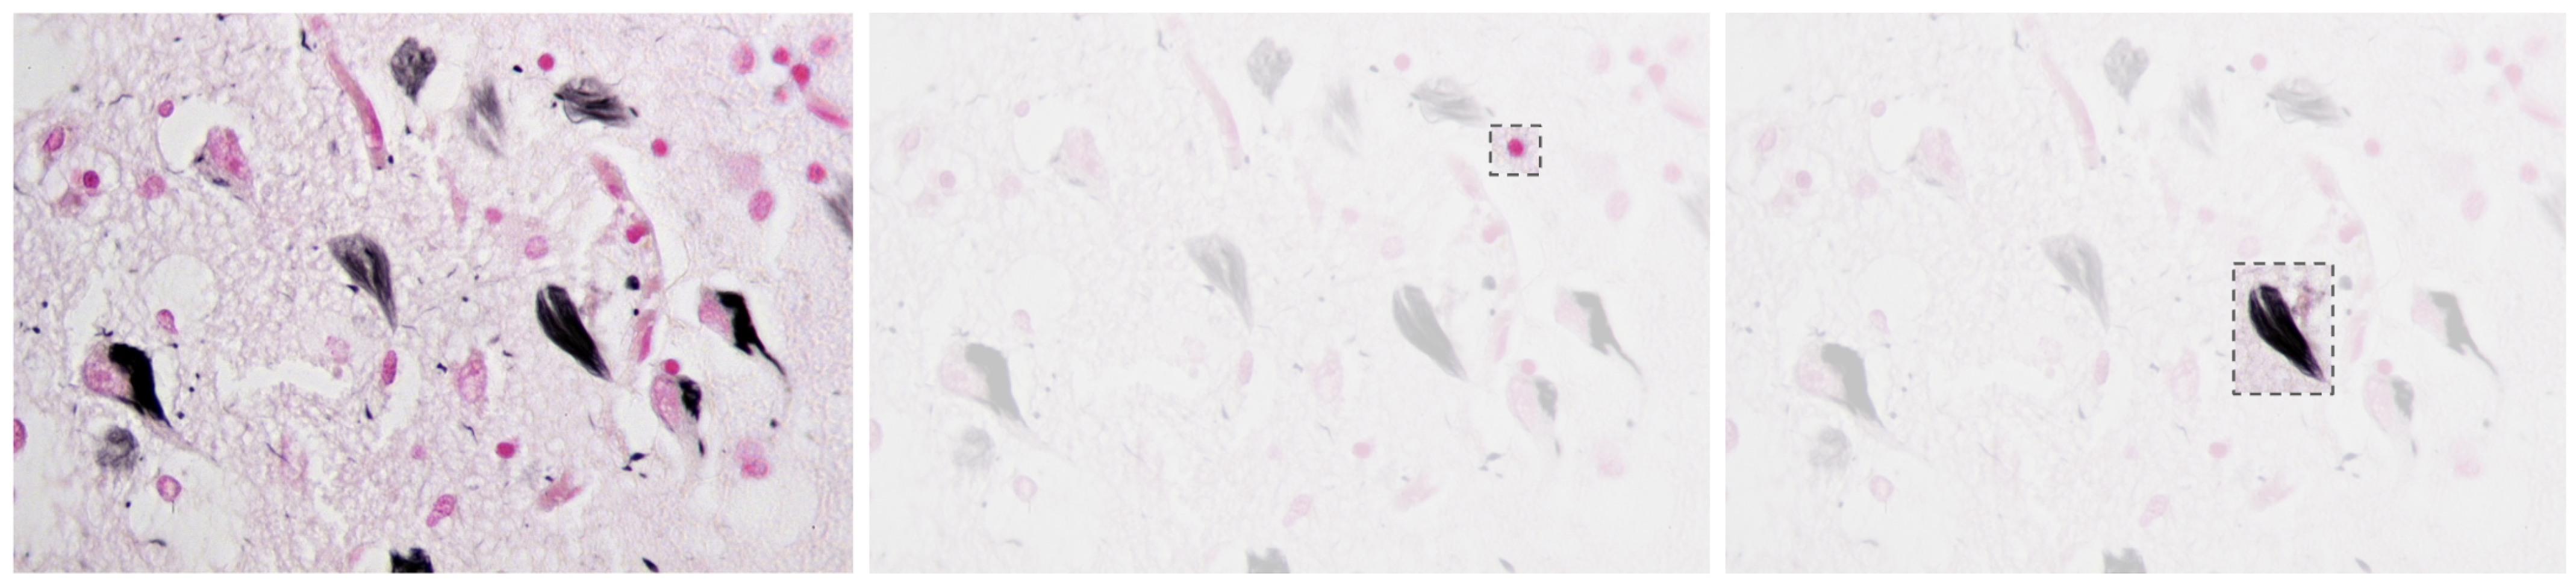

Alzheimer’s Disease (AD) is a progressive neurodegenerative disorder that causes amnesia, aphasia, and cognitive decline [1], among other symptoms. The neuropathology of AD is marked by cerebral atrophy caused primarily by the accumulation of two abnormal proteins: beta-amyloid (A) and tau [2,3]. Beta-amyloid aggregates extracellularly into plaques that disrupt neuronal communication, with the beta-amyloid 42 variant forming especially early and contributing significantly to the disease’s progression [1,4]. Concurrently, tau proteins missfold and accumulate intracellularly into neurofibrillar tangles, impairing axonal transport and contributing to synaptic dysfunction and neuronal death [2,5,6]. Figure 1 presents a histological section of brain tissue with Alzheimer’s markers, highlighting the characteristic amyloid plaques and neurofibrillar tangles, which are the hallmark pathological features of the disease.

Figure 1.

Alzheimer’s brain tissue with amyloid plaques (pink) and neurofibrillary tangles (black) [7].